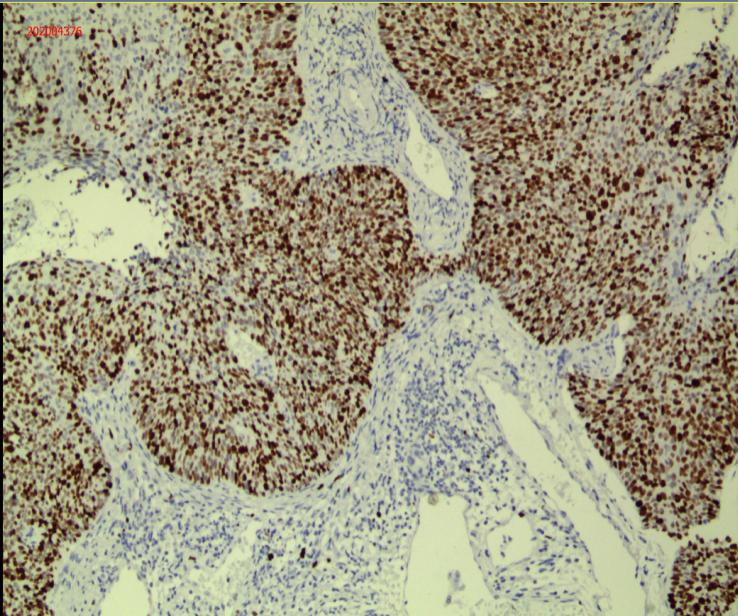

宫颈活检病理显示刘女士患有非角化型鳞状细胞癌